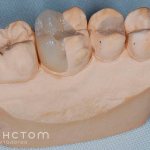

При кровоточивости десен возникших из-за краев металлокерамических коронок может пригодиться следующий раствор: понадобится по ложке таких трав: цветки зверобоя, бузина и листья земляники. Кипятить состав на слабом огне минут 15, снять с огня. Настаивать отвар 40 минут. Полоскать рот через каждые 2 часа в течении дня.